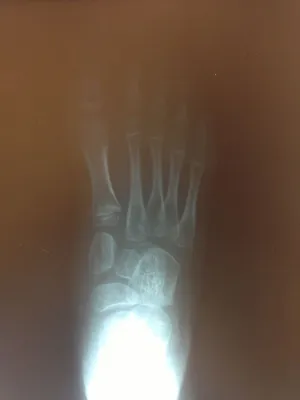

Pre-operative x-rays of the flatfoot with the talus deviated medially due to subluxing off the calcaneus causing the midtarsal joint to sublux laterally and uncovering of the talar head at the talo-navicular joint (left). The talus bone should line up with or be close to paralletl with a line drawn through the 1st metatarsal shaft (right). This is referred to as Meary's angle.

One case see an improvement in Meary's angle after surgical repair of the flatfoot with a subtalar joint implant which blocks the subluxation of the talus off of the calcaneus.